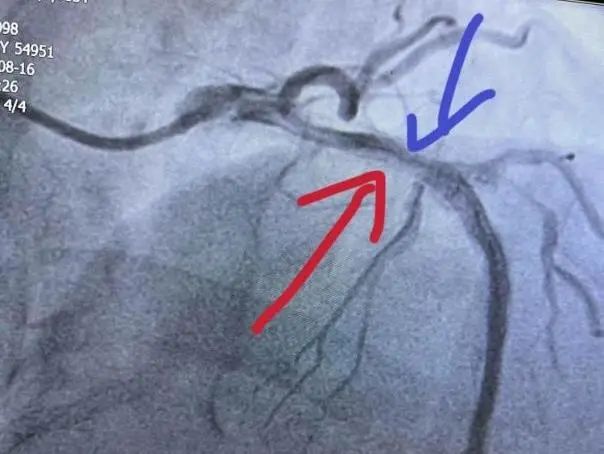

术中造影和OCT

LAD支架内再次发生狭窄伴明显钙化影像,刘长乐主任手术团队考虑LAD已经两层支架植入术后,当即决定手术策略:在OCT指导下使用shockwave冲击波球囊进行治疗。

术前OCT评估最小管腔面积(MSA)为2.48mm²,狭窄处为双层支架金属影,增生斑块为明显环形钙化病变。选用shockwave 3.0×12mm球囊实施钙化斑块碎裂术。